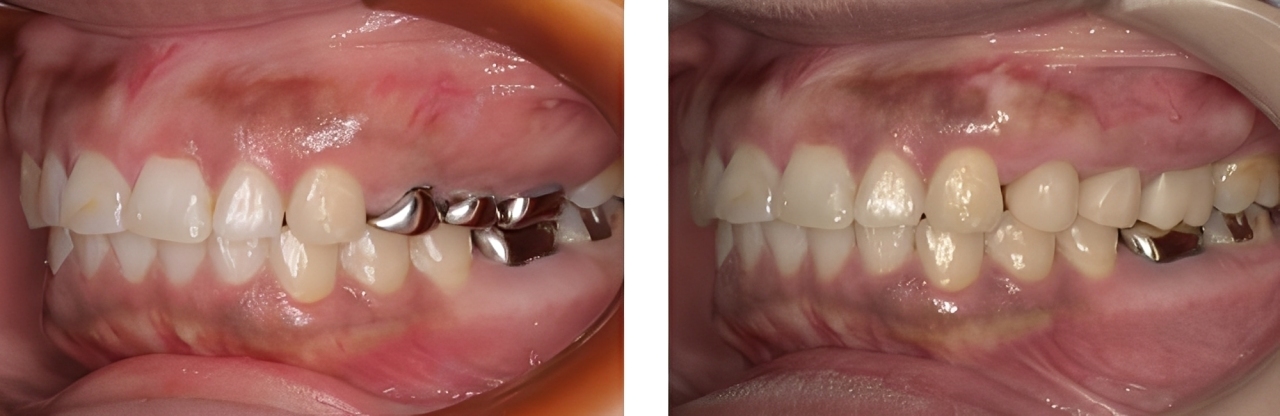

成人矯正

| 治療内容 | 掲載準備中 |

|---|---|

| 治療期間・回数 | 掲載準備中 |

| 費用 ※自由診療となります |

掲載準備中 |